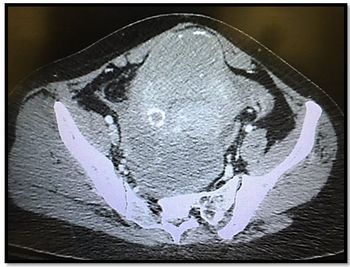

The 62-year-old describes lower abdominal “pressure” and using 2 pads/day; she reports a recent UTI. Review lab results and CT scan. What’s your diagnosis?

A 35 y/o woman presents with 3 wks lower abdominal pain that's worse with movement. Review exam, labs, CT scan. Your diagnosis?